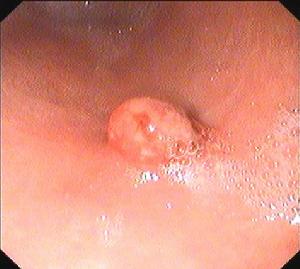

胃息肉1.增生性息肉此型息肉約占胃息肉的75%~90%,是炎性黏膜增生形成的息肉樣物,並非真正的腫瘤。息肉較小,一般直徑小於1.5cm,呈圓形或橄欖形,有蒂或無蒂,表面光滑,可伴有糜爛。組織學上可見增生的胃小凹上皮和增生的固有層腺體,上皮分化良好,核分裂象少見,固有層見炎性細胞浸潤,部分息肉伴有腸化生。少數增生性息肉可發生異型增生或腺瘤性變而產生惡變,但其癌變率一般不超過1%~2%。

2.腺瘤性息肉系來源於胃黏膜上皮的良性胃腫瘤,約占胃息肉的10%~25%。一般體積較大,呈球形或半球形,多數無蒂,表面光滑,少數呈扁平狀、條狀或分葉狀。組織學上主要由表面上皮、小凹上皮和腺體增生形成。上皮分化不成熟,核分裂象多見,可分為管狀、絨毛狀及混合型腺瘤,常伴有明顯腸化生和異型增生。息肉間質為疏鬆結締組織,有少量淋巴細胞浸潤。黏膜肌層無明顯增生,肌纖維無分散現象。本型息肉癌變率高,可達30%~58.3%,尤其瘤體直徑大於2cm、絨毛狀腺瘤、異型增生Ⅲ度者惡變率更高。

胃息肉胃息肉很少有陽性體徵,合併炎症時上腹部可有壓痛,出血多者有繼發性貧血表現。X線胃鋇餐透視和胃鏡檢查是診斷胃息肉的主要方法。X線胃鋇餐透視顯示胃腔內呈現圓形或半圓形邊界整齊清晰,表面平整的充盈缺損,多數在1cm左右大小,有蒂者可見其移動。胃鏡檢查對診斷實屬必要,鏡下可見胃壁黏膜上有圓形或半圓形隆,一般小於2cm。邊界清晰,表面光滑平整,色澤呈正常黏膜象或呈鮮紅色,質地柔軟,有蒂或無蒂,單發或多發。部分息肉呈菜花狀表現,其表面或有糜爛或有潰瘍。菜花狀息肉和體積大於2cm者有惡變之可能,活組織病理檢查有助於鑑別診斷。